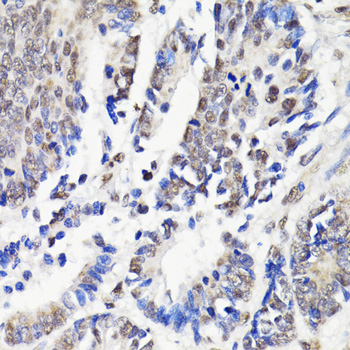

Immunohistochemistry of paraffin-embedded human colon carcinoma using NAV2 at dilution of 1:100 (40x lens).

Immunohistochemistry of paraffin-embedded human breast cancer using NAV2 at dilution of 1:100 (40x lens).